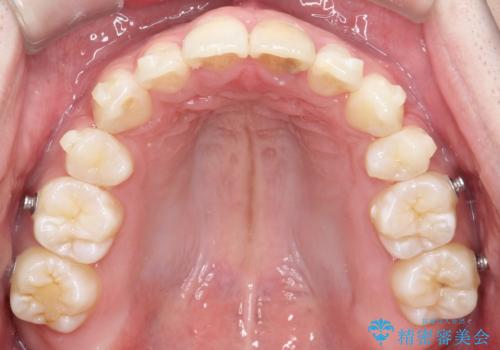

- 前歯が出ていることを主訴に来院されました。

臼歯関係が上顎前突傾向のため、上顎小臼歯を抜歯してインビザラインにて治療を行いました。

臼歯の咬合を作るために治療終盤ではゴムかけを行なっています。